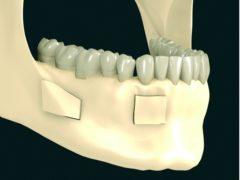

Przeszczep kości. W niektórych sytuacjach jest to jedyna skuteczna metoda odbudowy zanikłej kości. Zabieg polega na pobraniu fragmentu tkanki kostnej z innego miejsca jamy ustnej (albo przy większych przeszczepach z biodra) i następnym umocowaniu go w miejscu odbudowywanym. W ciągu kilku miesięcy następuje wgojenie się przeszczepu -€“ zamienia się on w pełnowartościową kość.